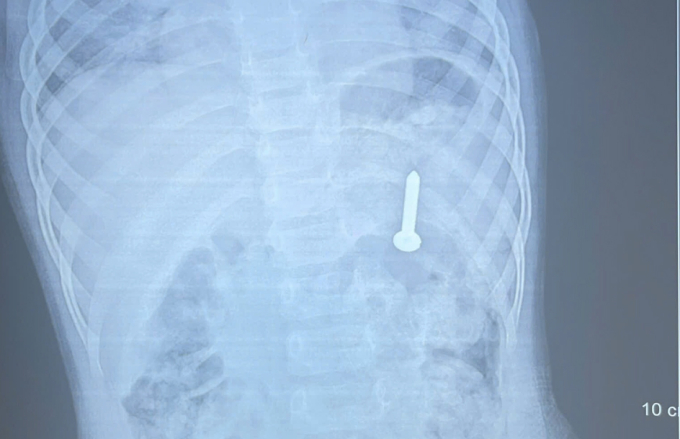

Ngày 14/4, Bệnh viện Đa khoa tỉnh Quảng Trị cho biết kết quả chụp X-quang xác định dị vật nằm trong dạ dày. Nếu không xử lý kịp thời, dị vật có thể gây thủng đường tiêu hóa, xuất huyết và nhiều biến chứng nguy hiểm.

Đinh vít nằm trong dạ dày bé gái. Ảnh: Bệnh viện cung cấp